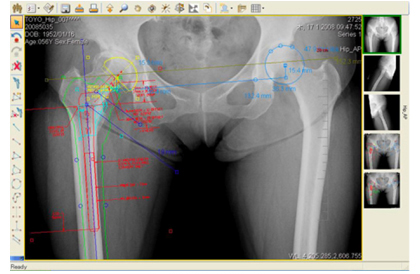

整形外科領域でのフィルムレスをめざすご施設向けに,デジタルプランニングツールOrthoPlanner Proを紹介します(図2)。複雑かつ専門的な作業が多い整形外科では,フィルムレスに切り替えることができず,多くの病院が頭を悩ませています。OrthoPlanner Proでは,日ごろ整形外科医師がフィルム上で行う計測や作図,テンプレーティングをモニタ上で実現。また,デジタルの利点を生かし,拡大率補正により正確な作業が可能となります。医師ごとに計測手順を登録できる「カスタム計測」により医師の負担を大幅に削減。モニタ上で骨をトレースする「アウトライン機能」,国内外主要インプラントメーカーのデータを豊富に実装した「テンプレーティング機能」により,完全フィルムレスを実現します。